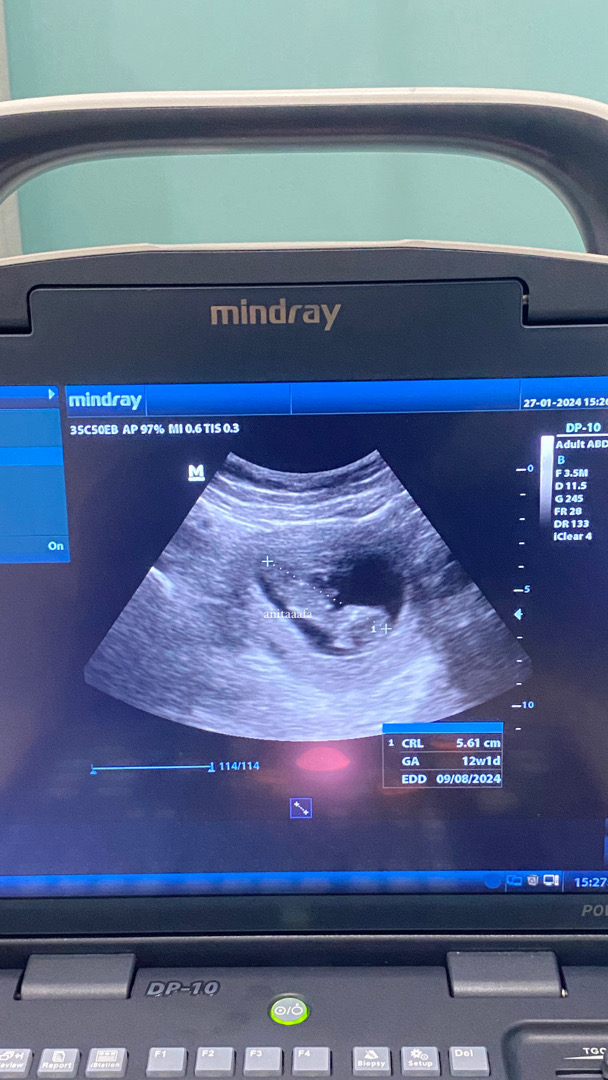

Alhamdulillah masyaAllah, setelah sebulan full overthinking krn kali terakhir check msh kantung aja di usia 6week. Hari ini sudah ada janin dan djj nya seneng bgt overthinking ku berkurang krn udah denger djj🥹❤️